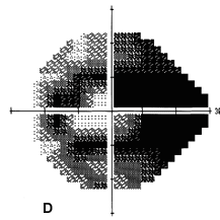

E. Visual Field Test

Humprey Visual Field test is the gold standard of visual field test for glaucoma. It helps to map-out the visual field defect of a glaucoma patient.

A patient could not tell how much visual vield he has lost because he himself does not aware of it not until the defect is being maped-out by this computer-assisted machine.

Fig: Progressive visual field loss with corresponding constricting view by a glaucoma patient